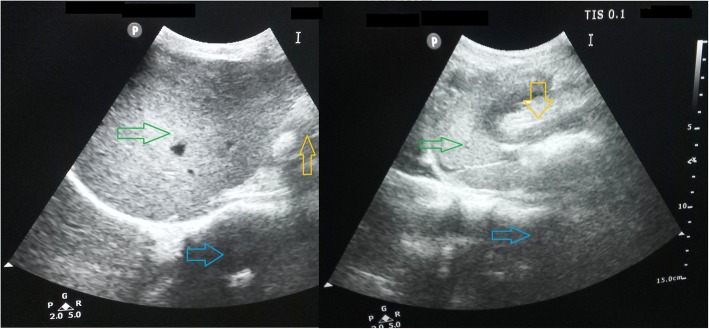

Fig. 5.

Post-operative Day 3 greyscale Ultrasonography of the liver (Green arrows) and epigastric region revealed the position of hypo-echoic omental fat (Yellow arrows) that was placed below the left lobe of the liver during operation and position of the pancreas (Blue arrows).USG shows no demonstrable collection in the operative field